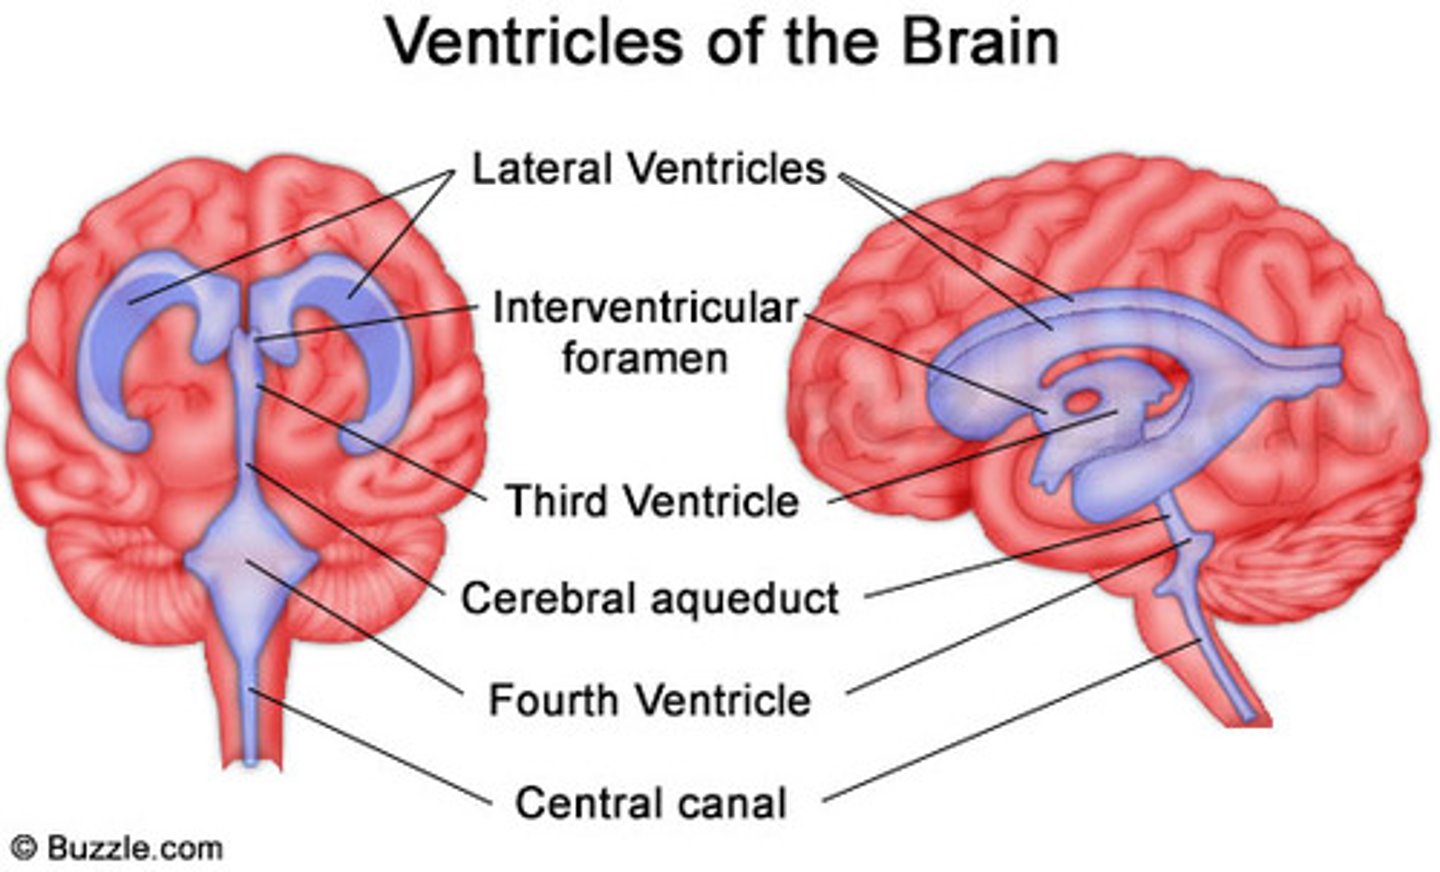

lateral ventricles

third ventricle

fourth ventricle

interventricular foramen

connects lateral ventricles to third ventricle

cerebral aqueduct

connects the third and fourth ventricles

choroid plexus

on the floor of all the ventricles, produces CSF

arachnoid villi